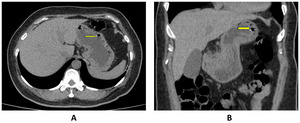

A 52-years-old female patient with underlying hypertension, dyslipidemia and anemia due to alpha thalassemia [hematocrit of 21% (normal range of 37-46%) was on treatment with proton-pump inhibitor for dyspepsia, persisting nausea and vomiting. She presented to our emergency department with vertigo, severe nausea and vomiting. She developed 2 episodes of severe frank-blood vomiting followed by syncope. She was found to have hypotension (BP 100/60 mmHg) and anemia (hematocrit 20%). A gastric lavage showed coffee-ground content. A computerized tomographic (CT) scan of abdomen was performed and showed numerous air bubbles in the wall of stomach at the fundus and along the greater curvature of cardia (Figure 1).

_and_coronal_(b)_ct_scan_images_showing_air_bubbles_in_gastric_wall_at_the_fundus.png)